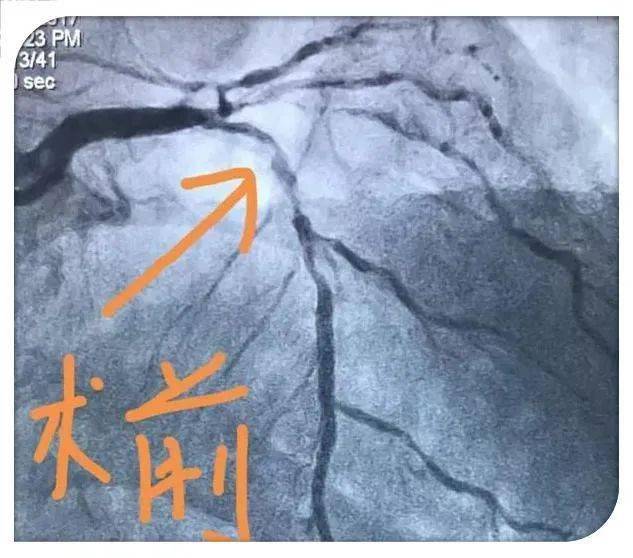

急诊冠脉造影示: 左主干加三支病变.

冠脉造影显示心脏三根血管堵塞两根